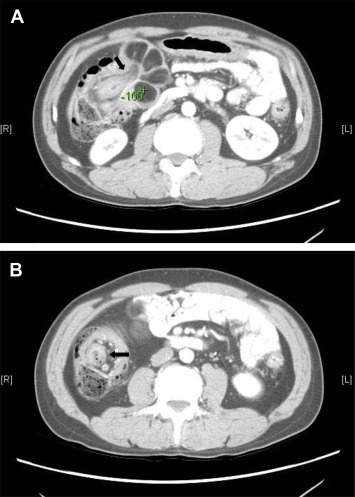

Endoscopic biopsy of the tumor showed normal colonic mucosa with focal necrosis and inflammation, but no evidence of malignancy. As a large amount of bloody stool passage developed after the colonoscope exam, we ordered a contrast-enhanced abdominal computed tomography (CT), which showed intussusception of the transverse colon by a giant polypoid tumor (Figures 2 A and 2B). Although the densiometry value of the tumor (−100 Hounsfield units, HU) was indicative of lipoma, liposarcoma could not be rule out because of its atypical presentation on the computed tomographic images (i.e., prominent septa and nodularity).

Contrast-enhanced abdominal computed tomography showing (A) intussusception of ...

Figure 2.

Contrast-enhanced abdominal computed tomography showing (A) intussusception of the transverse colon by a giant polypoid tumor; (B) with a bowel-within-bowel appearance (black arrow).

Abdominal ultrasonographic findings indicative of intussusception include the “crescent-in-doughnut sign” and “pseudokidney sign” [9] . An abdominal CT is another noninvasive diagnostic tool. Findings characteristic of lipoma on abdominal CT include the presence of smooth, demarcated margins with thin fibrous septa, and homogenous fatty densiometry values ranging from −40 HU and −120 HU [10] . Duration between the diagnosis of lipoma and intussusception has been reported to range from 1 day to 7 years [8] . Our patient developed intussusception 10 days after the colonoscopy.

Preoperative diagnosis of colonic intussusception is difficult to establish because the clinical presentations are not typically pathognomonic. Previous studies have shown that CT is the most useful and accurate diagnostic tool for intussusception, with 85% of the cases being correctly diagnosed [3] . In our patient, the CT appearance of bowel-within-bowel, which is described as “sausage sign” on longitudinal section and “target sign” on transverse section, is a typical presentation of intussusception. A polypoid tumor as the leading point was also identified. The densiometry value indicated lipoma. However, due to the atypical CT presentation with prominent septa and nodularity, we could not exclude the possibility of liposarcoma. A surgical approach with en bloc resection without reduction is recommended for colonic intussusception because of the high malignancy rate of the leading point and the possibility that the reduction procedure may cause the malignant tumor to spread.